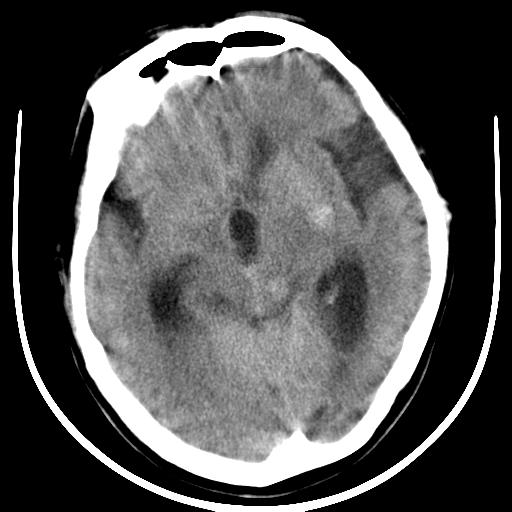

标题: CT16838:男58岁,意识不清2小时,请会诊出血部位该如何写。 [打印本页]

标题: CT16838:男58岁,意识不清2小时,请会诊出血部位该如何写。

1)脑干、左侧桥小脑臂及小脑蚓部出血破入蛛网膜下腔。2)左侧基底节区灶性出血,不排除钙化灶。3)脑室系统少量积血。4)脑积水。

(患者病情危重,出现不自主运动——是引起图像质量不佳的主要原因)

脑干左侧原发性脑出血破入脑室系统及蛛网膜下腔出血伴梗阻性脑积水。左侧基底节区原发性脑出血。脑萎缩。

脑干左侧原发性脑出血破入脑室系统及蛛网膜下腔出血伴梗阻性脑积水。左侧基底节区原发性脑出血可能性大,钙化不除外。